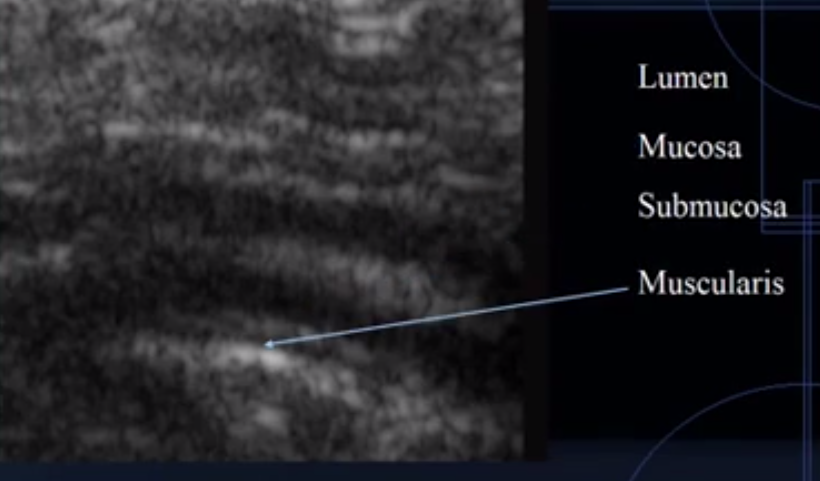

What does this image show?

Intestine

Which is the lumen?

Which is the mucosal layer?

Which is the submucosa layer?

Which is the muscularis layer?